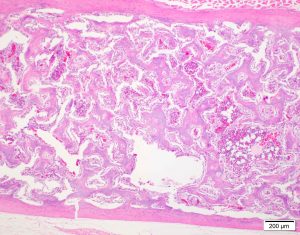

- normal in laying hens

- endosteal proliferation of basophilic trabeculae

- does not obscure the normal cortical bone

- normal bone marrow fills the intertrabecular space